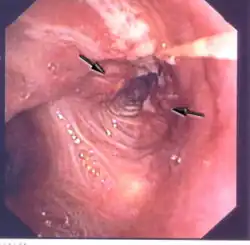

Le cancer du poumon peut être vu sur les radiographies thoraciques et le scanner. Le diagnostic est confirmé par une biopsie. Ceci se fait généralement par bronchoscopie, ou par biopsie guidée par scanner. Le traitement et le pronostic dépendent du type histologique du cancer, de son stade (degré de dissémination), et de l'état général de santé du patient.

Diagnostic

il n'existe pas de règle précise déclenchant les explorations à partir des premiers symptômes, le plus souvent peu expressifs[127],[3]. Mais dans tous les cas, lorsque le cancer est suspecté, le diagnostic doit déboucher sur une preuve histologique, et sur la délimitation de son extension.

La radiographie thoracique est la première mesure à prendre si un patient se plaint de symptômes pouvant suggérer un cancer du poumon. Ceci peut révéler une masse évidente, un élargissement du médiastin (qui suggère une extension aux ganglions lymphatiques qui s'y trouvent), une atélectasie (affaissement), une inflammation (pneumonie) ou un épanchement pleural. En l'absence de signes radiographiques, mais si les soupçons sont élevés (par exemple, un gros fumeur avec hémoptysie), une bronchoscopie ou un scanner peuvent donner l'information nécessaire. La bronchoscopie ou la biopsie guidée par scanner sont souvent utilisées pour identifier le type de tumeur[3].